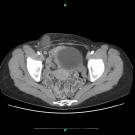

Elizabeth J. Donovan, MSPAS, PA-C; Mohammed M.H. Kalan, MD

A 61-year-old woman presented to the emergency department with swelling and tenderness of the right groin, low-grade fever, and chills. The bulge had been present in the right groin for 2 months. Her newest...